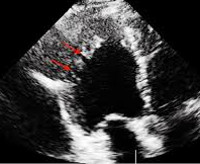

• Ультразвуковое исследование (Эхо-КГ). Это основной способ визуализации нефизиологической структуры мышечного слоя левого желудочка. На патологию указывает утолщение стенки камеры из-за массивных трабекул, выступающих в полость с объемными межтрабулярными пространствами, особенно в области вершины и боковой стенки. Толщина некомпактной части в два раза выше нормальной, так как при использовании допплеровского картирования в желудочке обнаруживаются турбулентные кровотоки. Дополнительно указывается тип заболевания - при изолированной форме другие аномалии в структуре органа не видны.